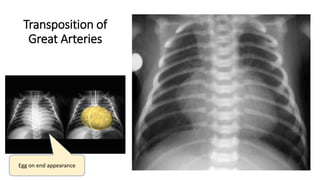

Transposition of

Great Arteries

Egg on end appearance